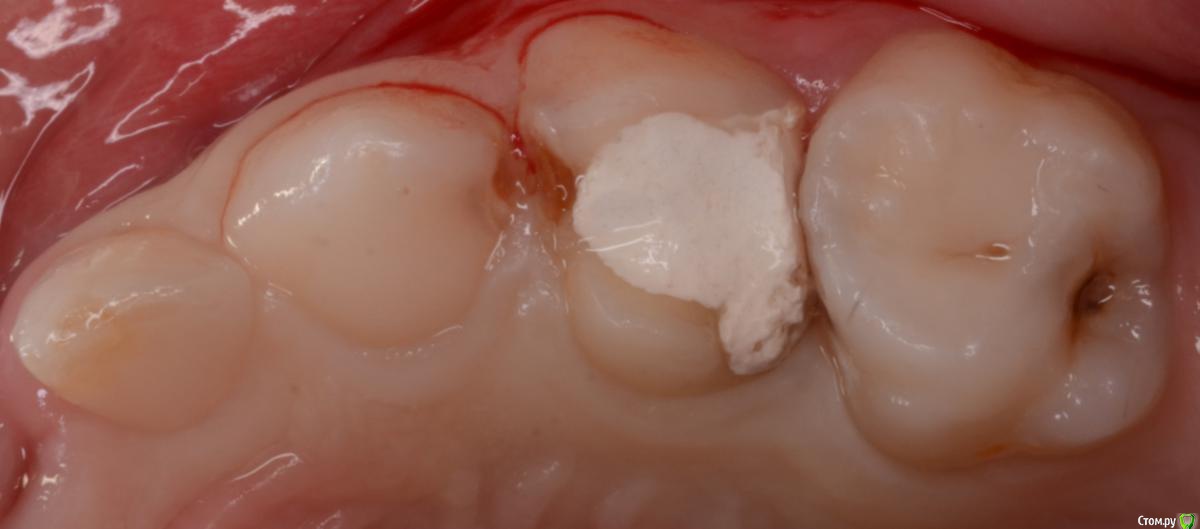

CRAZYDUCK Опубликовано 11 февраля, 2020 Автор Поделиться Опубликовано 11 февраля, 2020 Лечение 3.6 , 7.5 Обратите внимание на десну дистально на 3.6 . Ее можно заправить флоссом и платком 4 Ссылка на комментарий

CRAZYDUCK Опубликовано 11 февраля, 2020 Автор Поделиться Опубликовано 11 февраля, 2020 Случай перелечивания через год после лечения в наркозе . Появился кариес на контактных поверхностях . Лечили в ЗакС . Это лечение одного сегмента . Всего пролечила 4 сегмента в ЗакС .девочке 4 годика . На момент последнего лечения очень устала ,на контакт шла с трудом . Но смогли договориться . В наркозе я не лечу , только в ЗакС . В наркоз отправляю к врачам , в навыках и знаниях которых уверена .Лечили кариес клыка и пятого , четвёртый был в наркозе нарощен со всех сторон , поэтому - коронка . 2 Ссылка на комментарий